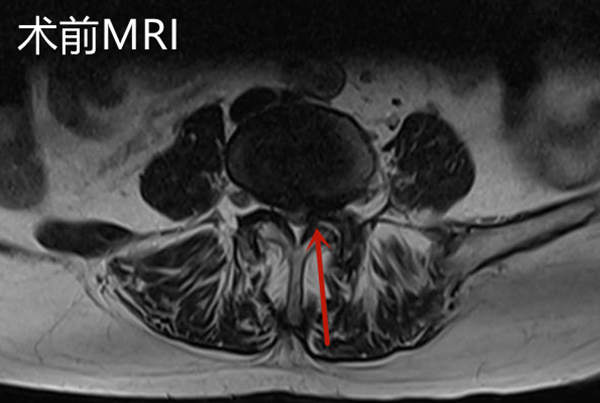

邱奶奶入院后查腰椎磁共振顯示L4/5椎管嚴(yán)重狹窄,神經(jīng)根受壓,明確診斷為腰椎管狹窄癥。腰椎骨狹窄癥是老年人群常見(jiàn)的腰椎退行性疾病。狹窄可以發(fā)生在中央椎管、側(cè)隱窩以及椎間孔等部位,由于椎管或神經(jīng)根管的狹窄,致使椎管內(nèi)神經(jīng)受壓,神經(jīng)功能障礙,可表現(xiàn)為腰痛、下肢疼痛或麻木,隨著病情的發(fā)展可出現(xiàn)下肢運(yùn)動(dòng)及感覺(jué)障礙。

手術(shù)后復(fù)查腰椎MRI顯示:相應(yīng)的椎管狹窄及神經(jīng)根壓迫已解除,手術(shù)后第2天邱奶奶便可下地行走,腰痛及左下肢疼痛緩解,復(fù)查腰椎磁共振見(jiàn)L4/5左側(cè)狹窄已完全解除。手術(shù)后第4天,患者順利出院,沒(méi)有出現(xiàn)任何手術(shù)并發(fā)癥。